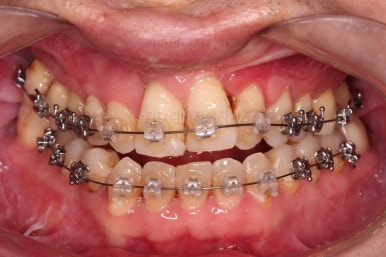

6. 마무리와 치료종료

부산구순구개열교정 종료 시의 입안의 모습입니다.

위아랫니 정렬이 잘 되었고, 치아 갯수가 위아래가 다르지만 교합도 나쁘지 않게 마무리가 되었습니다.

대문니 2개가 예후가 안좋긴 하나 양옆 치아들과 유지철사로 부착해 두어 최대한 오래 조심히 써보기로 했습니다.

7. 전후 비교사진

치열이 정렬이 잘 되었고요.

웃을 때 보이는 치열의 느낌, 얼굴과의 조화 등 모든 부분이 좋아졌습니다.